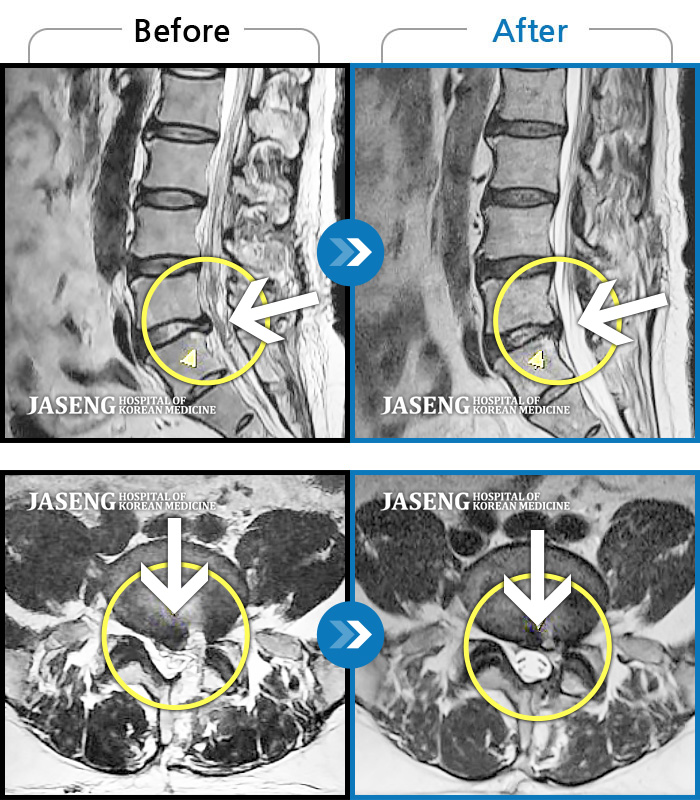

허리디스크

도움받은 사례

광주 · 이일석 원장

우측 허리 뻐근한 통증, 우측 허벅지부터 발목까지 이어지는 당김

촬영시기

2023.03.07 ~ 2023.12.23

2023.12.29